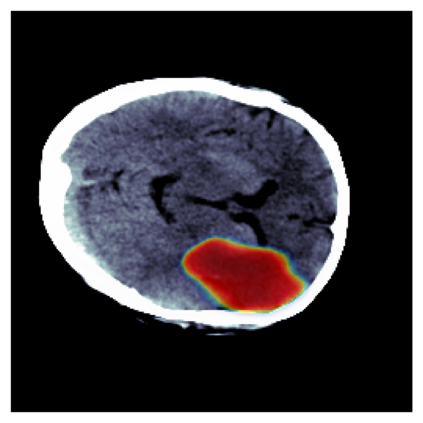

The sigmoid activation is the standard output activation function in binary classification and segmentation with neural networks. Still, there exist a variety of other potential output activation functions, which may lead to improved results in medical image segmentation. In this work, we consider how the asymptotic behavior of different output activation and loss functions affects the prediction probabilities and the corresponding segmentation errors. For cross entropy, we show that a faster rate of change of the activation function correlates with better predictions, while a slower rate of change can improve the calibration of probabilities. For dice loss, we found that the arctangent activation function is superior to the sigmoid function. Furthermore, we provide a test space for arbitrary output activation functions in the area of medical image segmentation. We tested seven activation functions in combination with three loss functions on four different medical image segmentation tasks to provide a classification of which function is best suited in this application scenario.